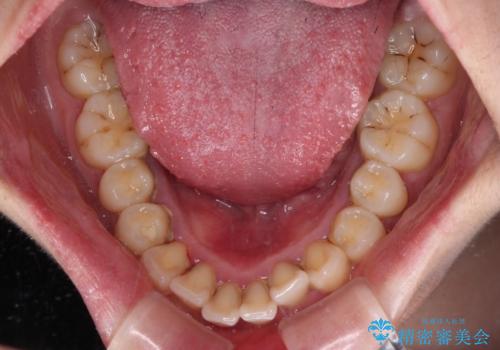

- 下唇に跡がつくほどに飛び出した上顎前歯を気にして来院された患者様です。

来院された時から4本の抜歯が必要であることを理解されていらしており、通法通り上下左右の第一小臼歯4本を抜歯し、ワイヤー装置にて矯正治療を行うこととしました。